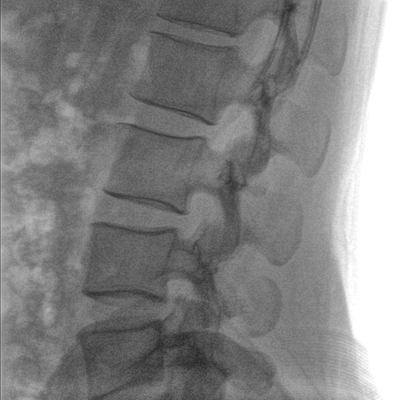

C形臂和工作站一體化設計,機架結構緊湊,占地面積小,移動靈活輕便。一人即可完成操作,適合在擁擠的手術室內使用,節約手術室空間,方便醫生的臨床操作。

C形臂機架在解鎖狀態下可實現多角度懸停,確保設備操作安全平穩。

大尺寸液晶顯示器,圖像顯示清晰細膩;顯示器可大角度旋轉,滿足臨床多角度觀察圖像的需要。

在球管和平板探測器兩端,分別加裝了激光定位系統,滿足不同擺位無射線下的定位需求,降低醫患輻射劑量的同時,提高臨床工作效率。